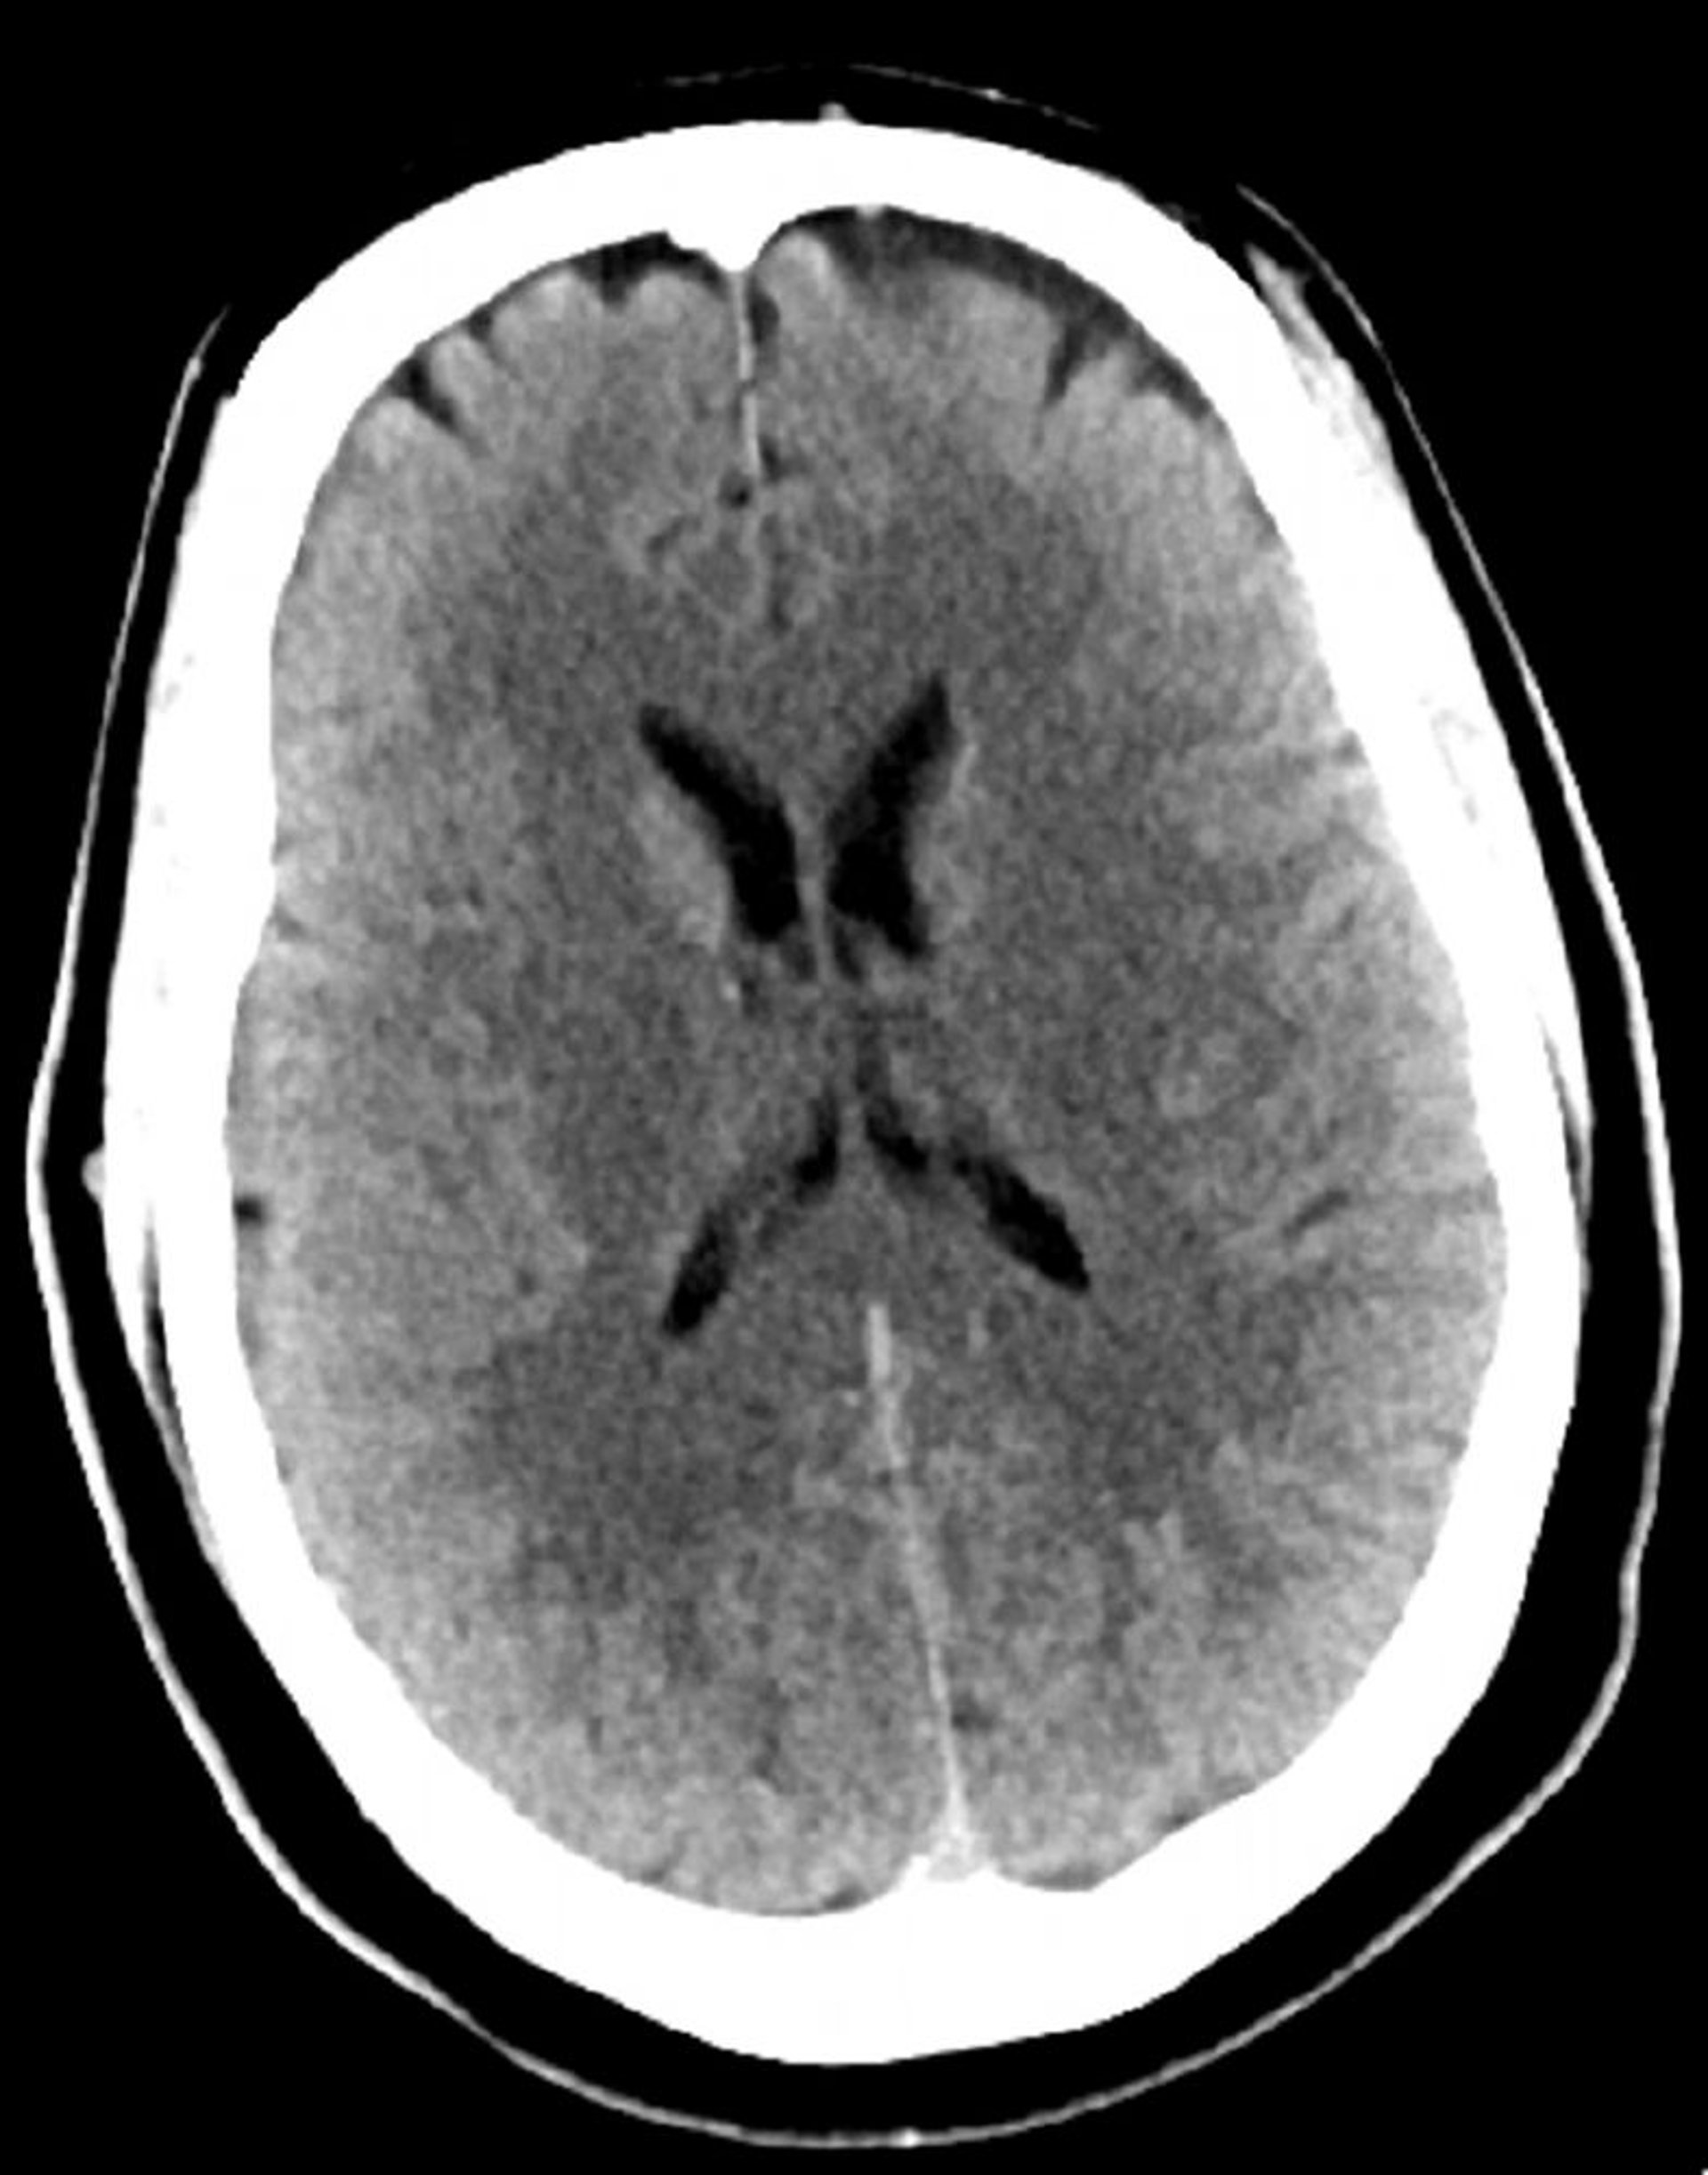

正常な頭部CT(成人,30歳)―スライド4

これは30歳の若年成人の正常な頭部CT画像である。脳実質の内外に髄液や出血はみられない。白質と灰白質の区別は維持されている。脳室の大きさと脳溝のパターンは正常である。